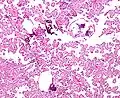

Micrograph of a choroid plexus papilloma. H&E stain.

The tumor is neuroectodermal in origin and similar in structure to a normal choroid plexus. They may be created by epithelial cells of the choroid plexus.